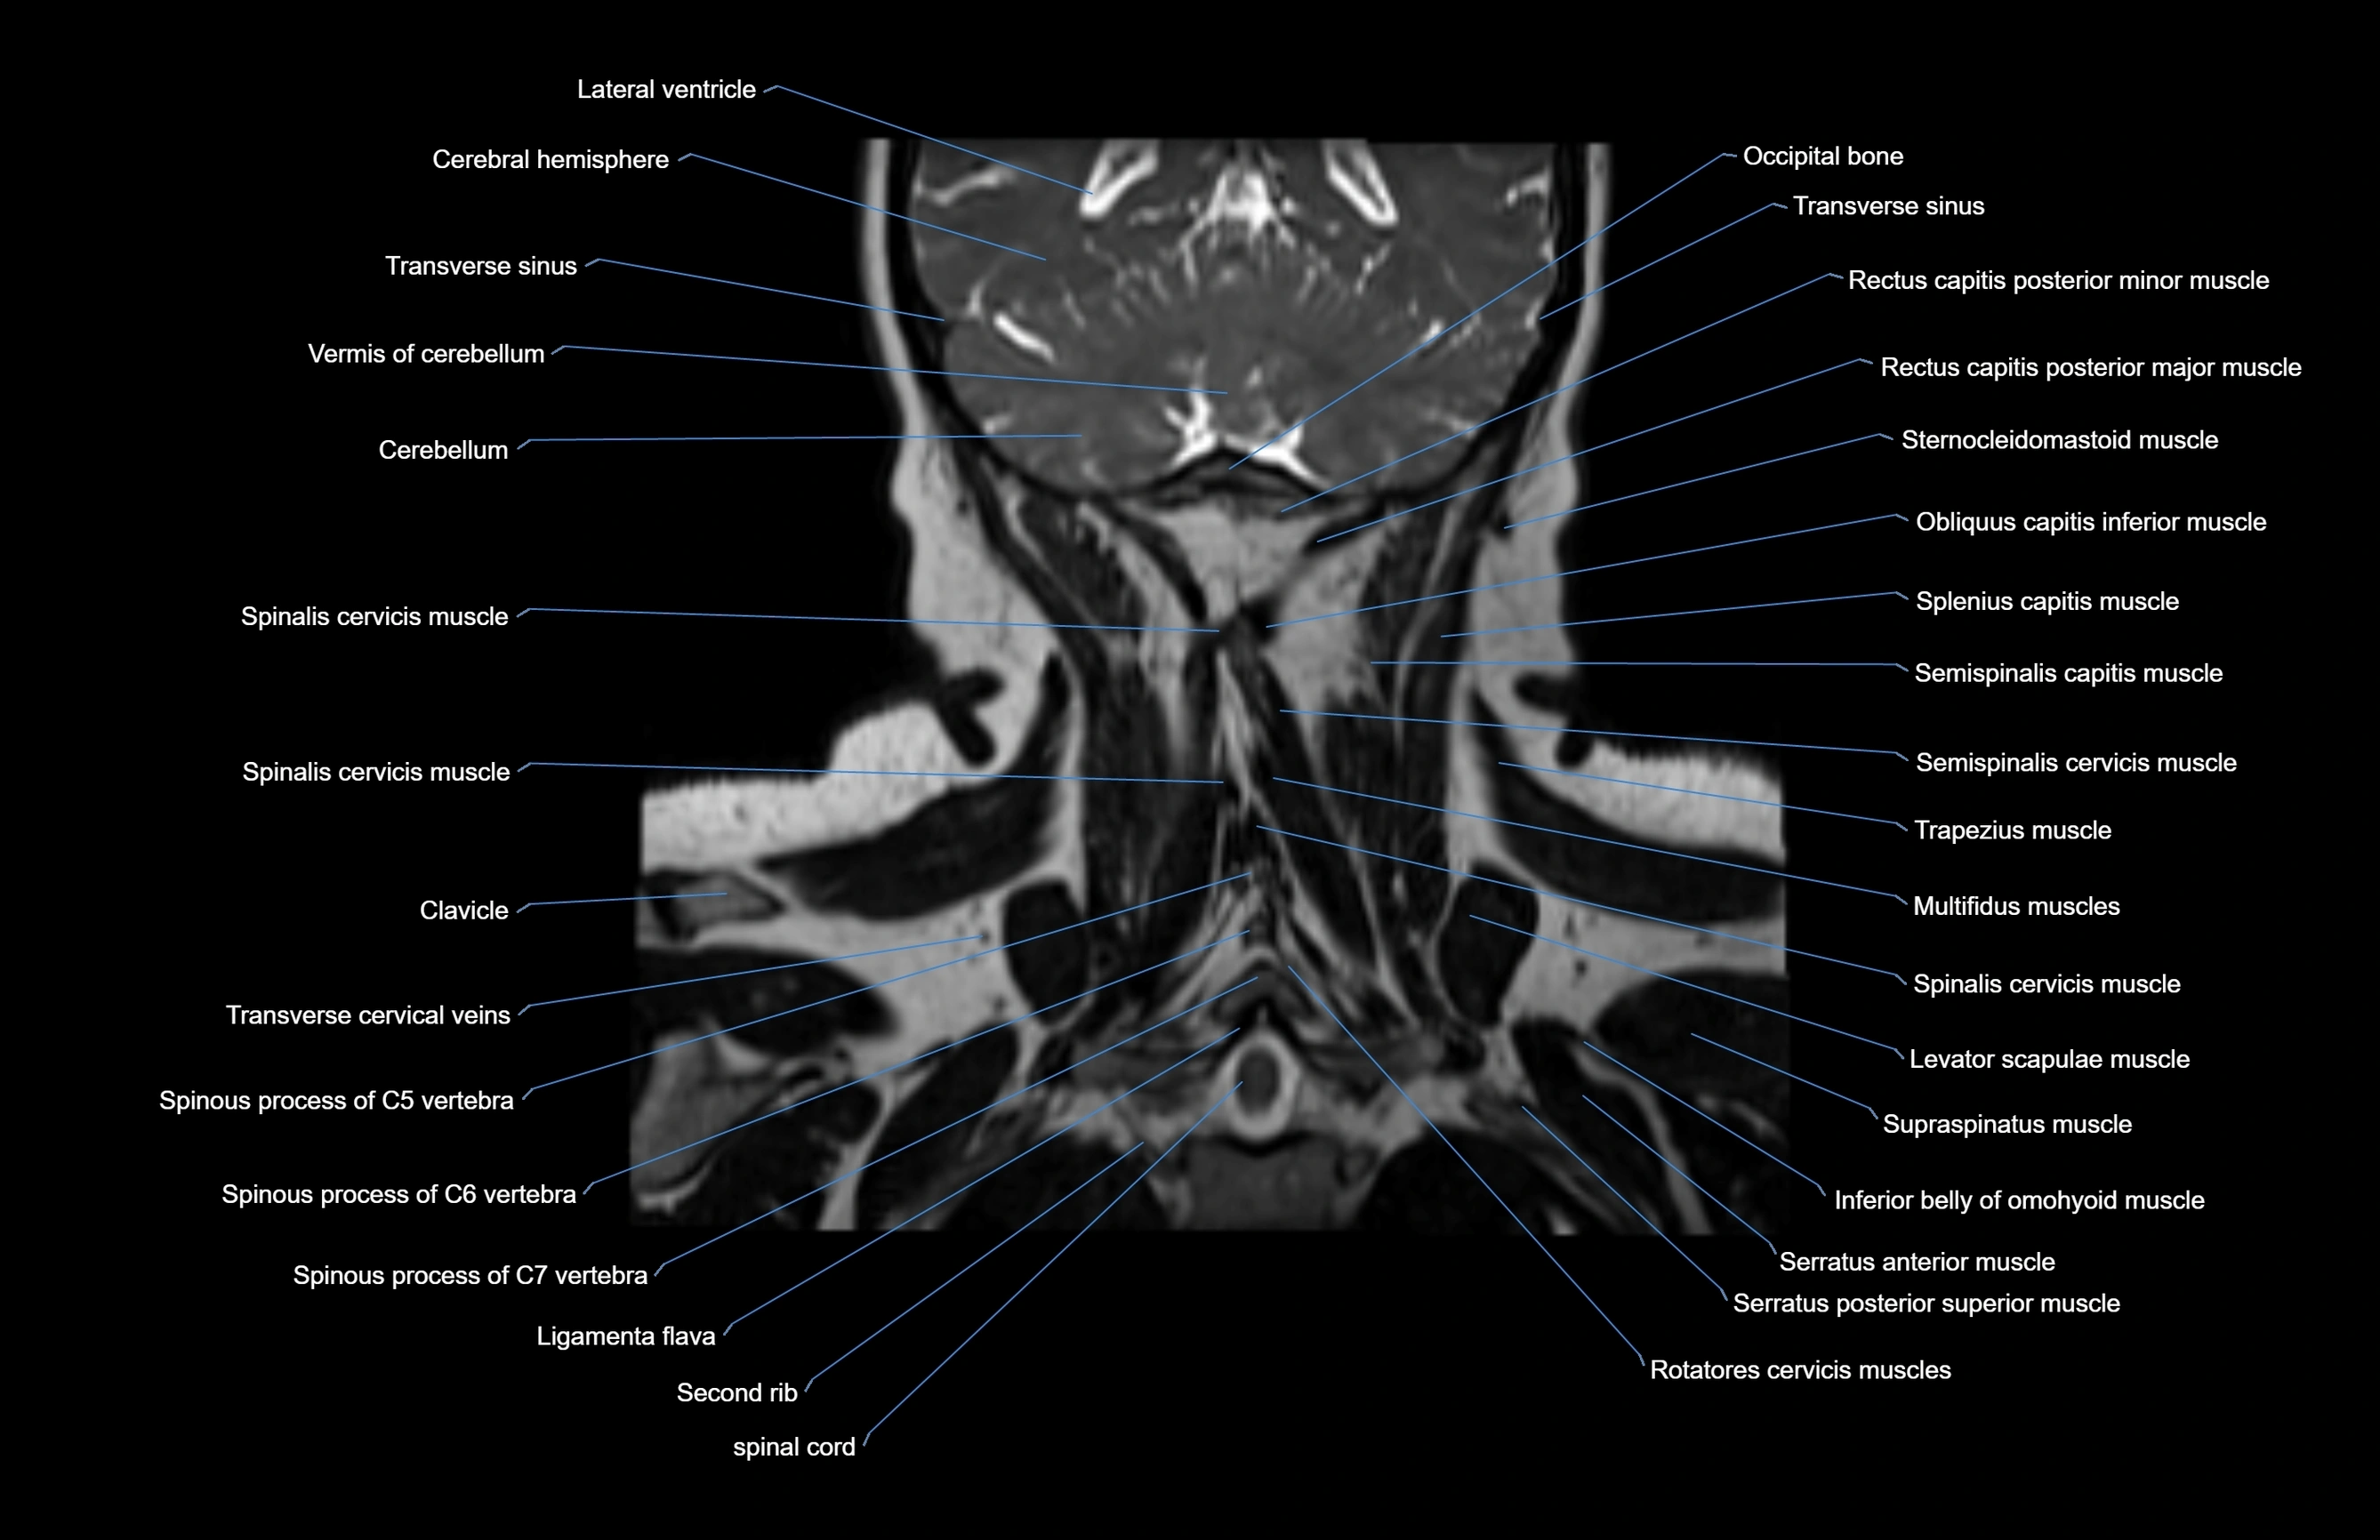

- Cerebellum

- Clavicle

- Inferior belly of omohyoid muscle

- Ligamenta flava (Ligamentum flavum)

- Multifidus muscles

- Occipital bone

- Paramedian lobule

- Rectus capitis posterior major muscle

- Rectus capitis posterior minor muscle

- Rotatores cervicis muscles

- Semispinalis capitis muscle

- Semispinalis cervicis muscle

- Serratus posterior superior muscle

- Spinal cord

- Spinalis cervicis muscle

- Spinous process of vertebra

- Splenius capitis muscle

- Splenius cervicis muscle

- Sternocleidomastoid muscle

- Styloglossus muscle

- Supraspinatus muscle

- Trapezius muscle